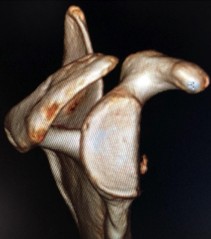

- 3D-CTによる科学的な評価 手術して終わりではなく、術後6ヶ月、1年と経過を精密な3D-CTで追跡。移植した人工骨がどのように自身の骨と馴染み、形態が安定していくかを詳細に検証しています(2024年 日本肩関節学会発表データより)。